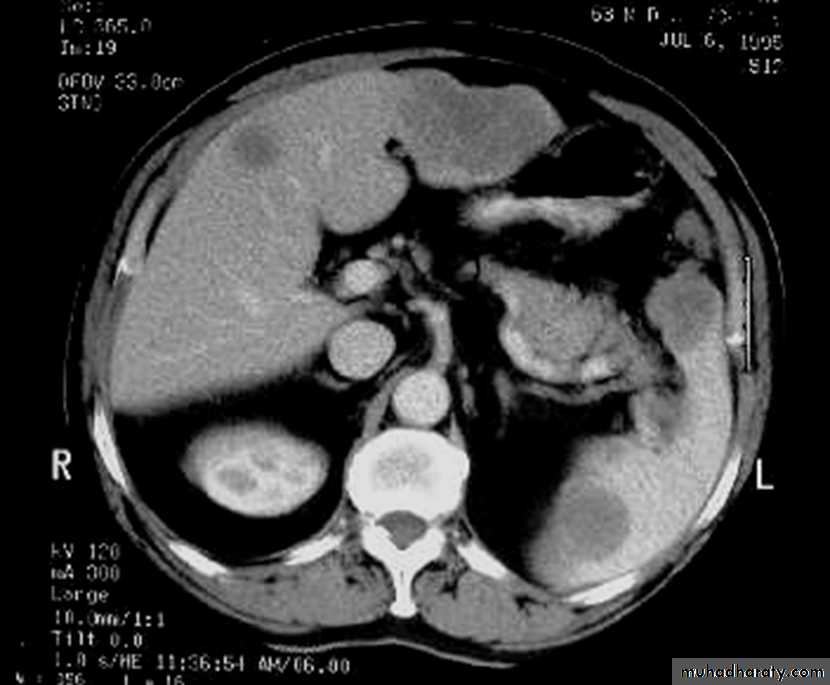

apple core lesion in the descending colon

Multiple lesions are seen in the liver and spleen consistent with metastases